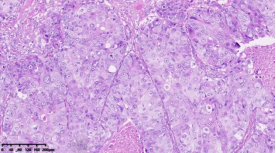

通過(guò)進(jìn)一步基因表達(dá)譜測(cè)序,對(duì)組織形態(tài)學(xué)和免疫組化水平界定的TNBC亞型的基因變異情況進(jìn)行分析,篩選各亞組之間的差異表達(dá)基因及表達(dá)意義探究,結(jié)果顯示:1.免疫治療相關(guān)的生物標(biāo)記物MSI-H、TMB-H,作為一個(gè)低頻發(fā)生事件,在TNBC中不太可能常規(guī)作為免疫治療有效性的評(píng)估手段;TNBC的MSI發(fā)生機(jī)制可能與結(jié)直腸癌不同、突變熱點(diǎn)不同。2. 整個(gè)研究隊(duì)列中基因表達(dá)存在明顯差異,充分顯示了患者個(gè)體間差異的存在,從分子水平揭示了TNBC是一種高度異質(zhì)性腫瘤。3. TP53基因變異率發(fā)生最高,提示在TNBC形成中可能扮演非常重要的角色。4. TNBC分型的基因表達(dá)聚類分析方面存在差異(圖2),這些差異基因參與了多種不同的生物學(xué)通路,篩選特異的分子標(biāo)記物或靶向治療的靶點(diǎn)以期指導(dǎo)臨床治療。

圖2. 基于組織形態(tài)學(xué)及免疫組織化學(xué)標(biāo)記物的TNBC亞型的基因表達(dá)聚類分析